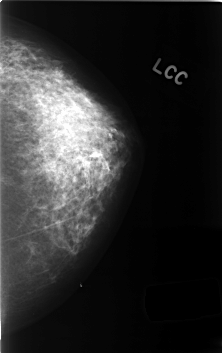

C_0413_1.LEFT_MLO

C_0413_1.LEFT_CC

LEFT_MLO LINES 4400 PIXELS_PER_LINE 2896 BITS_PER_PIXEL 12 RESOLUTION 50 NON_OVERLAY

LEFT_CC LINES 4584 PIXELS_PER_LINE 2880 BITS_PER_PIXEL 12 RESOLUTION 50 NON_OVERLAY